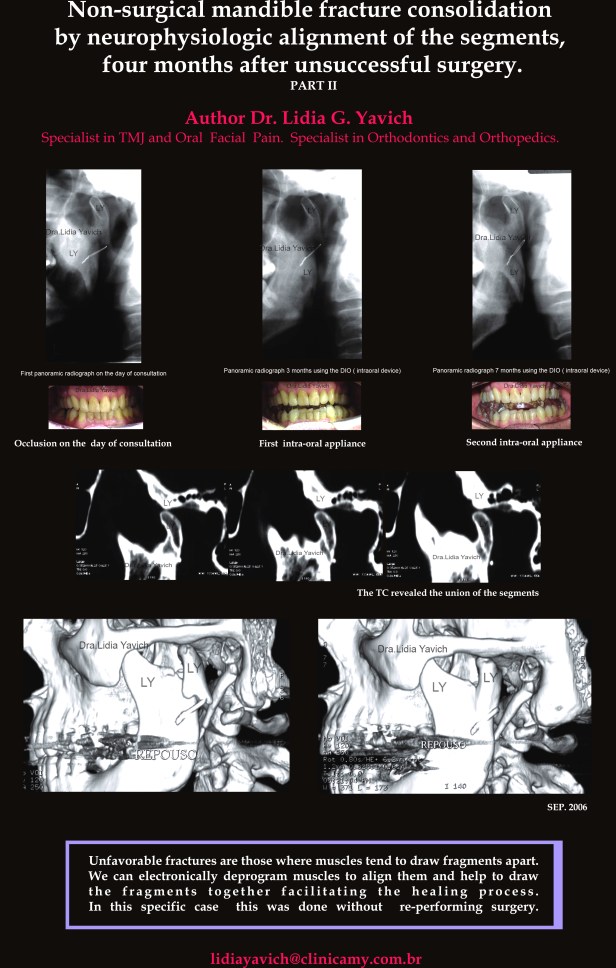

Uma segunda radiografia panorâmica foi solicitada três meses após o inicio do tratamento.

A nova radiografia panorâmica mostrou a melhora da posição do côndilo mandibular e finalmente quatro meses após este ultimo controle uma terceira radiografia panorâmica foi solicitada onde pode se observar a união da fratura.

Imagem comparativa do côndilo mandibular esquerdo na primeira radiografia panorâmica do paciente no dia da consulta (4A).

Segunda radiografia panorâmica três meses após (4B)

Terceira radiografia panorâmica (4C) quatro meses após o segundo controle mostrando a melhora da posição do côndilo mandibular e a união do osso.

OBSERVAR A VERTICALIZAÇÃO DO FIO METÁLICO DA CIRURGIA

Imagem comparativa do côndilo mandibular esquerdo na primeira radiografia panorâmica do paciente no dia da consulta (4A), segunda radiografia panorâmica três meses após (4B) e terceira radiografia panorâmica (4C) quatro meses após o segundo controle mostrando a melhora da posição do côndilo mandibular e a união do osso.

As imagens frontais da oclusão habitual no dia da consulta, quatro e sete meses após iniciado o tratamento estão também inseridas nesta imagem.

Uma nova TC foi solicitada e claramente mostra a união da fratura, sem o paciente ter sido submetido a uma nova cirurgia e sem ter usado nenhuma fixação maxilomandibular (MMF).

Reconstrução em 3D mostrando a falta de união do côndilo mandibular esquerdo após quatro meses da cirurgia e a posterior união do côndilo mandibular após o tratamento neurofisiológico.

Fraturas onde os músculos tendem a trazer os fragmentos juntos são mais favoráveis que aquelas fraturas onde os músculos tendem a separar os fragmentos.

O deslocamento dos segmentos da fratura é observado nas fraturas do côndilo mandibular. O tipo, mais comunmente observado é o deslocamento ântero-medial por causa da ação do músculo pterigoideo lateral.

A habilidade de posicionar espacialmente a mandibula, através da medição do comprimento de repouso dos músculos mastigatórios pode ser um auxiliar importante na recuperação das fraturas do côndilo mandibular.